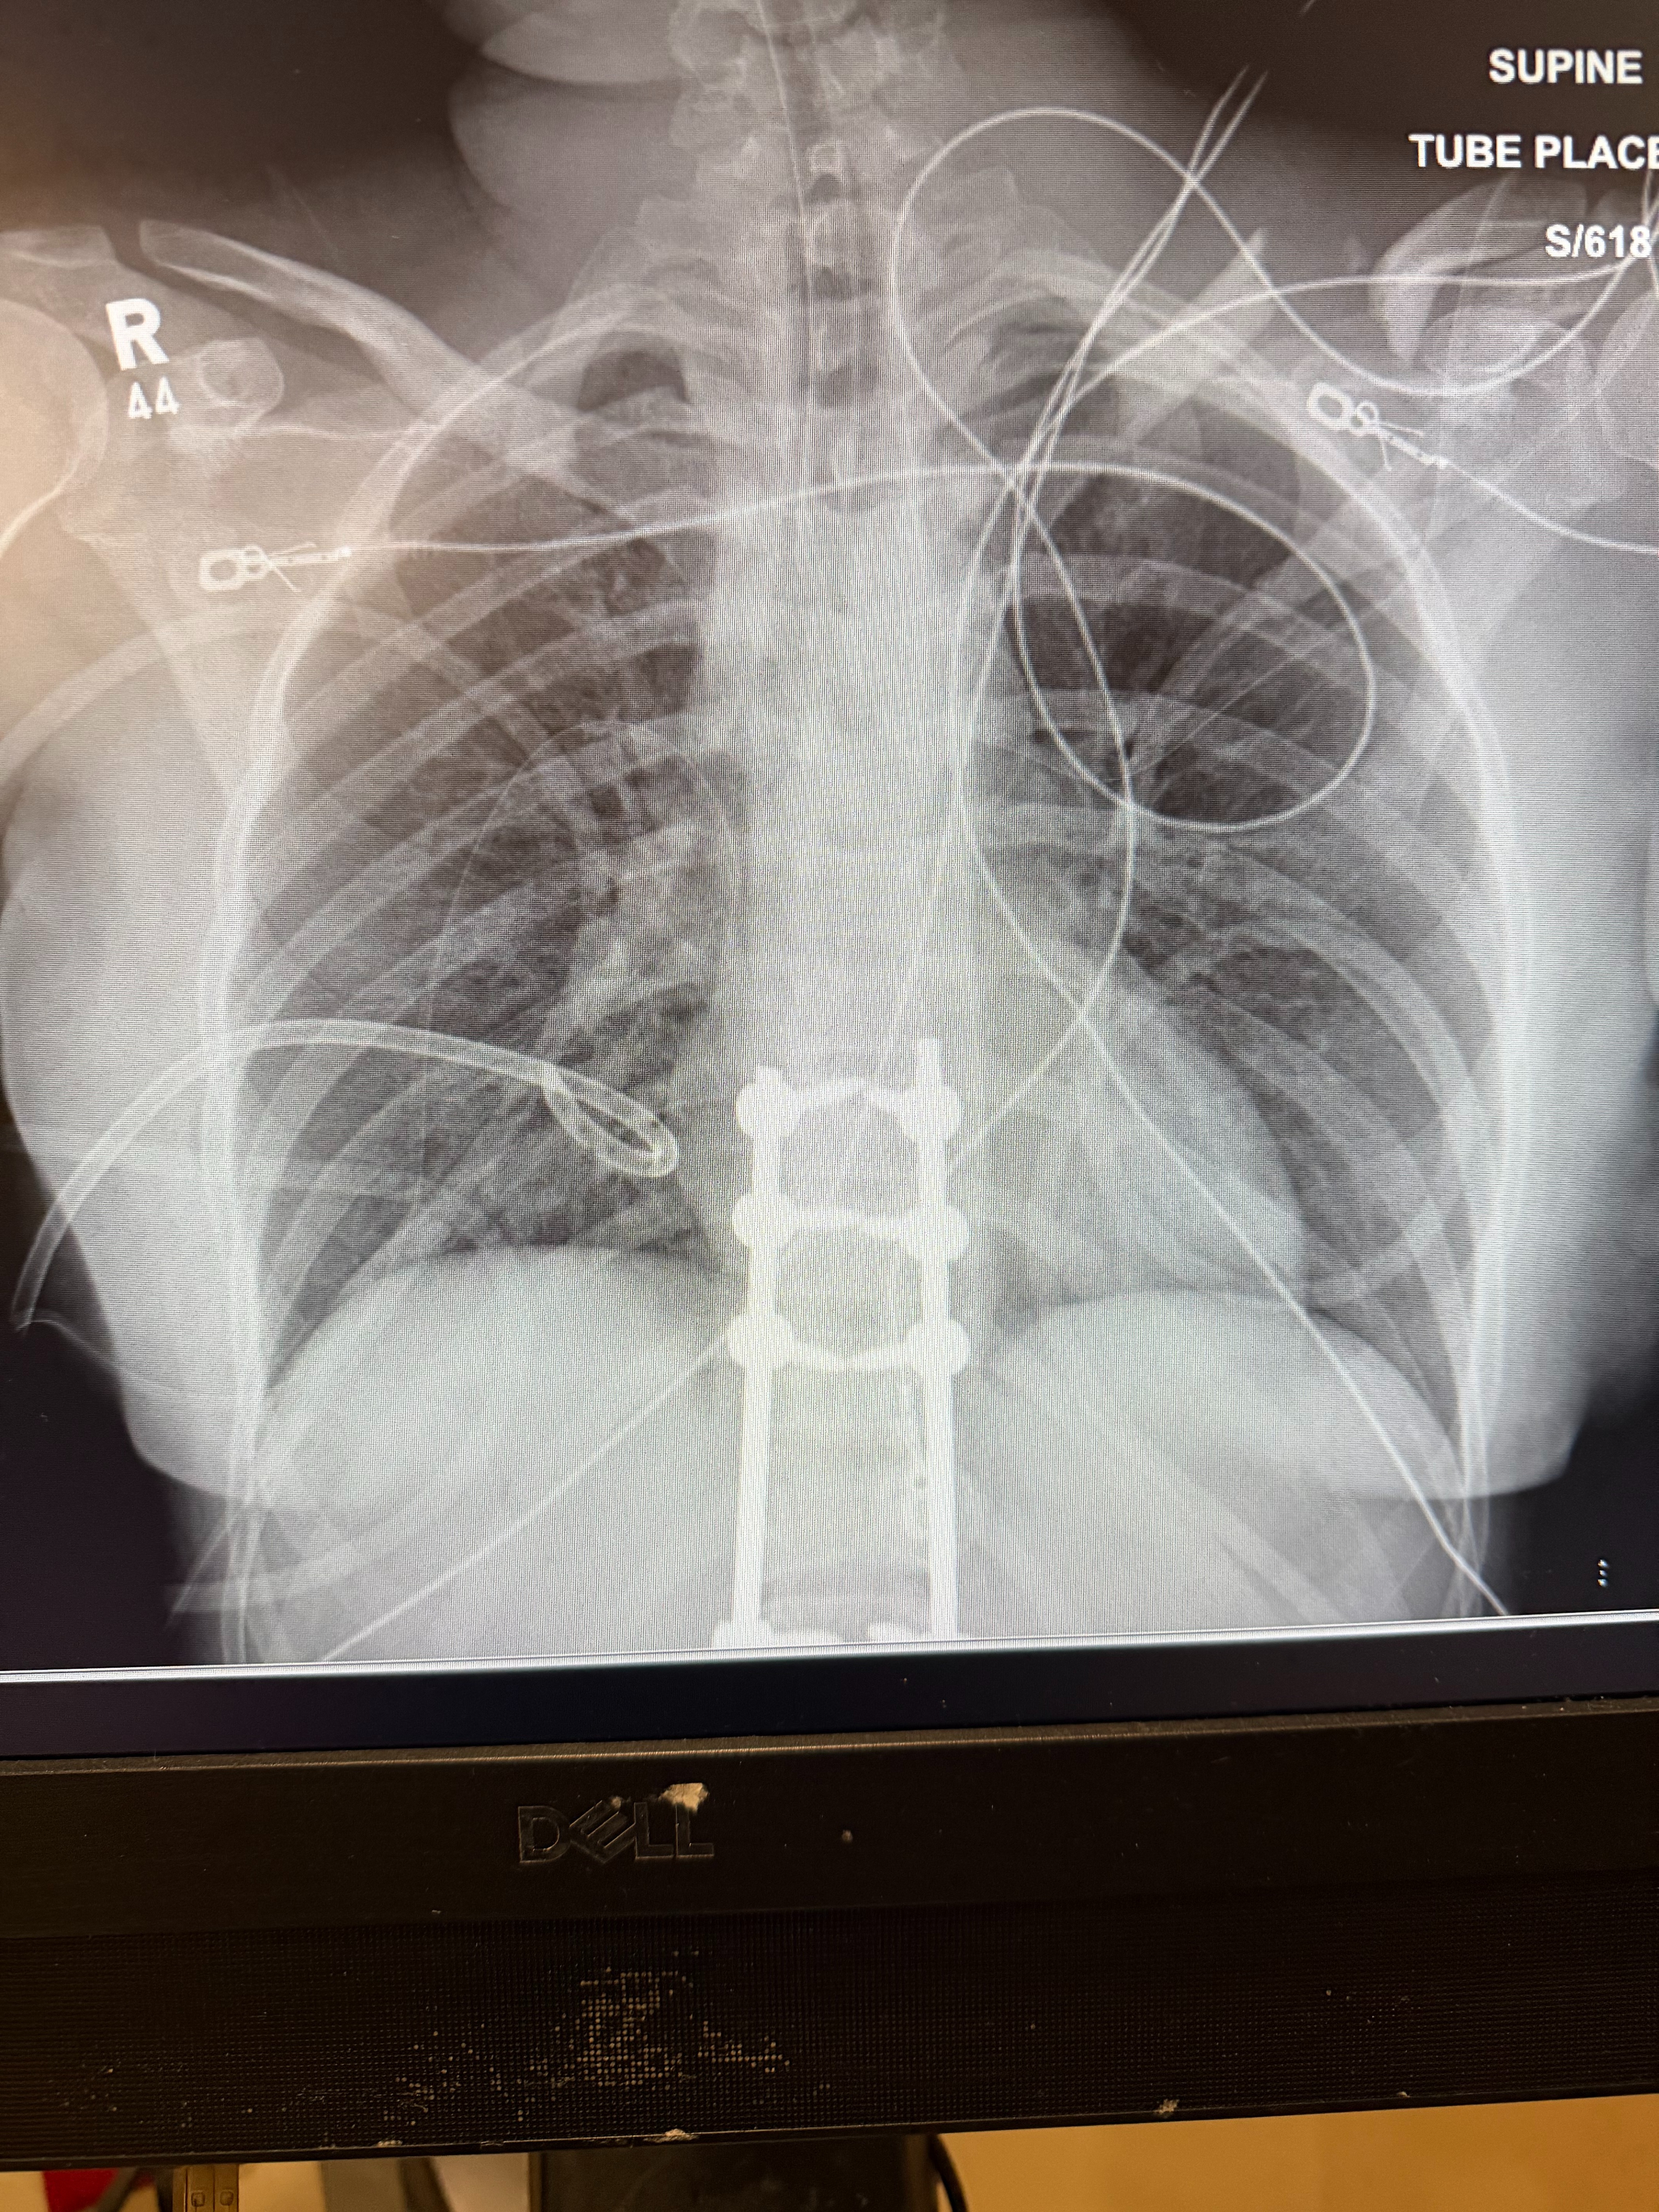

Hi Friends and Family, I am doing well. Thanks, everyone, for your love and support. I love you all and appreciate everyone. My goal for the moment is 75k, I do not exactly know what my total bills will be as I am still currently going through the motions. The next couple of months are going to be a little bit different, so please bear with me. I am currently recovering from spinal fusion surgery where 2 small rods and 6 screws were put in, a broken clavicle surgery where 14 screws and 2 plates were put in, punctured lungs, and fractured ribs. I know that times are really tough for everyone, especially right now. Every day brings new challenges, but I am determined to get stronger and healthier. The funds raised will go directly toward my medical expenses, rehabilitation, and living costs while I will be unable to work. Your kindness and generosity will help ease the burden and allow me to focus on my recovery.